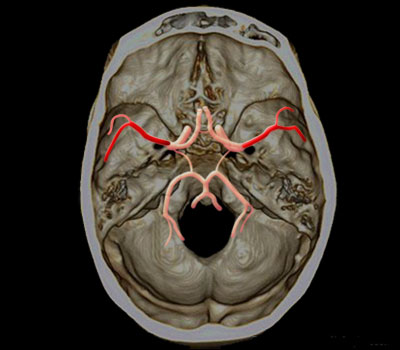

Artères cérébrales moyenne

Territoire de l’artère cérébrale moyenne